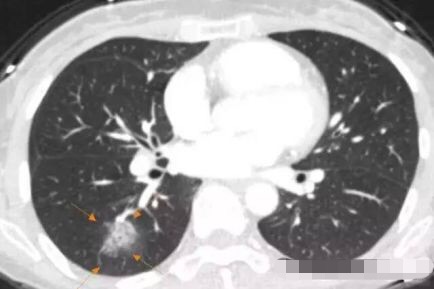

3.元芳,你看,这个也像GGO,还有一个小空洞,但它是一个隐球菌感染(肺里面长蘑菇了),不是肺癌,不用担心。